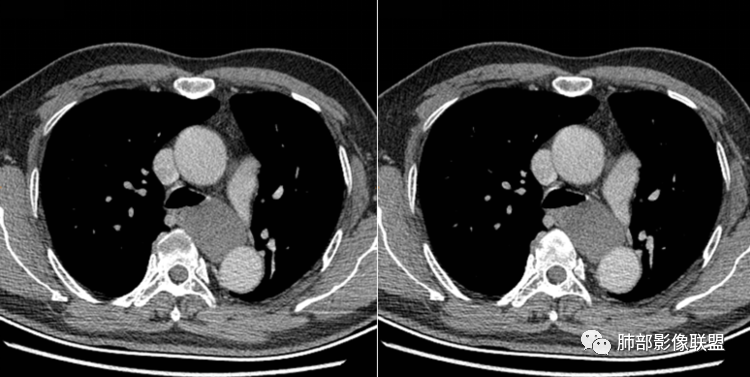

患者,男,43岁,无意间发现纵隔肿物,无胸闷胸痛,无心慌气短,无咳嗽,无吞咽困难等不适。体检发现的,无症状。

气管、左主支气管后方,食道左侧囊性占位,壁薄且均匀、光滑。气管及左主支气管受压凹陷、变形。

食道也受压变形、移位。